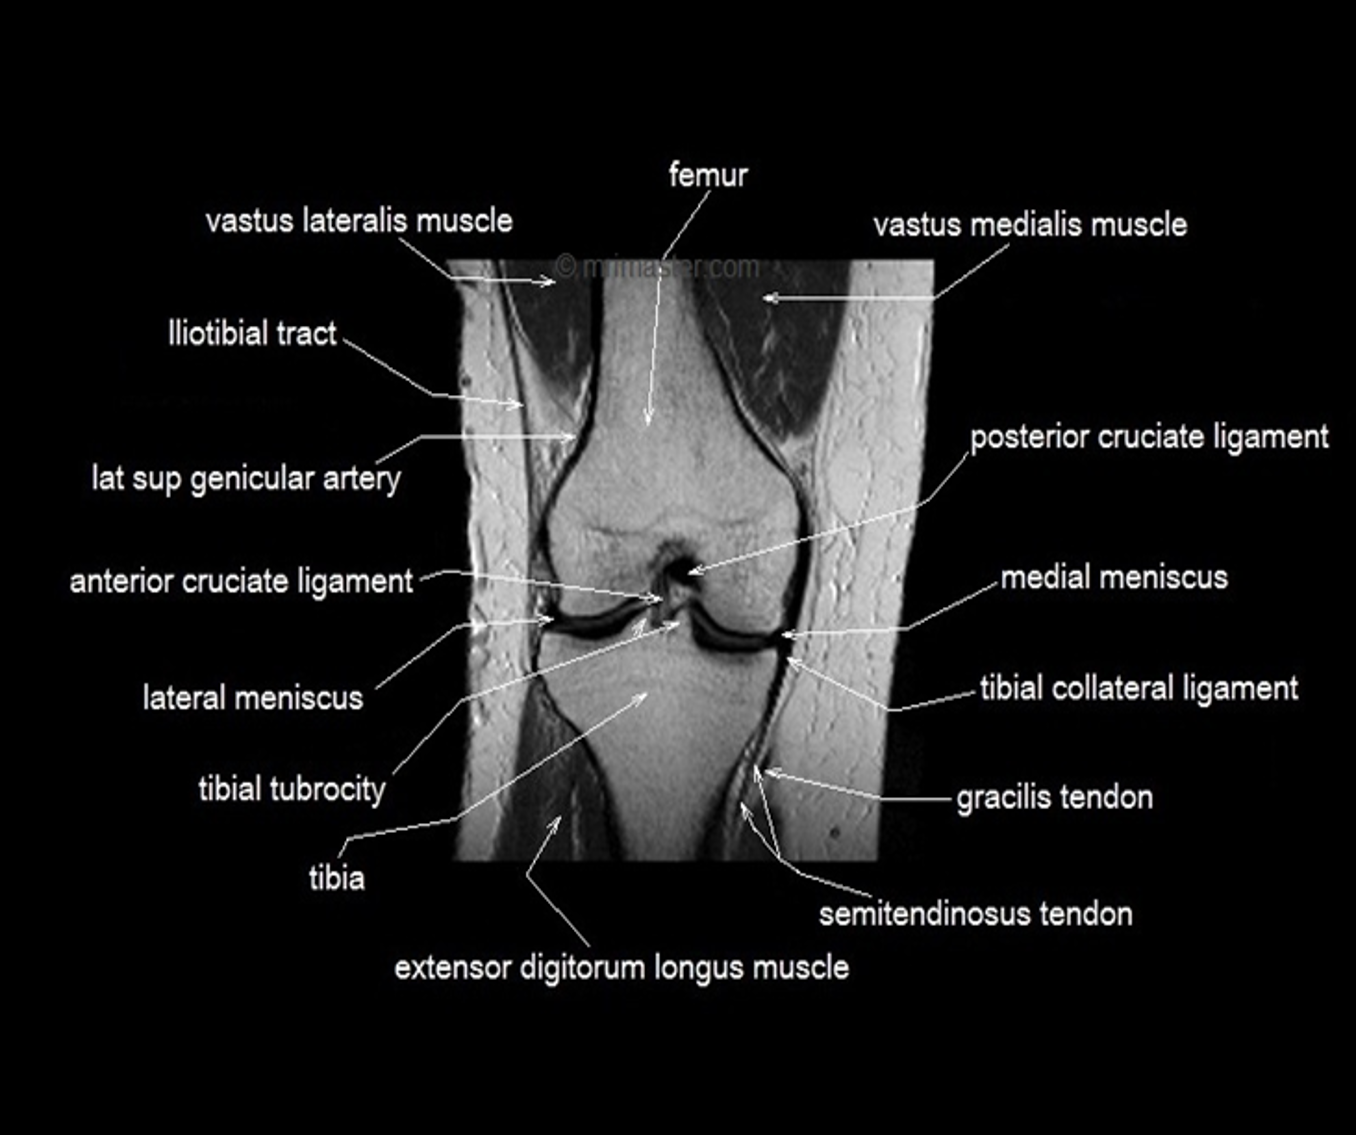

MRI is also very useful for demonstrating injury to soft tissues such as muscle, tendons and ligaments and is particularly useful in knee injuries.

- MRI is widely used for detection of abnormal joint fluid.

- MRI is the best examination for sports injury.

- Meniscal and ligamentous tears (e.g. in the knee)